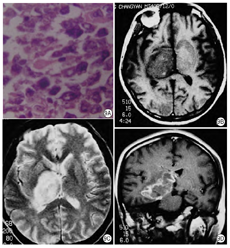

病理改变:HIV脑炎早期大脑形态无明显改变,以后出现不同程度的脑萎缩,多见局部萎缩表现,如额叶、颞叶比较明显,晚期可见脑室扩张,脑组织明显萎缩,重量减轻。HIV脑炎的病灶分布于大脑白质和灰质中,深部灰质(基底核、脑干核团)病变比较严重;也可见脑组织发生灶性或大片坏死。镜下检查,HIV脑炎以多核巨细胞形成于小胶质结节比较有一定特征性,故又有"多核巨细胞脑炎和结节性脑炎"之称。特征表现为广泛分布的小胶质结节浸润,即小胶质细胞增生,聚集成小结节。一般多核巨细胞和小胶质细胞结节可视为HIV脑炎的病理诊断依据(图2A、图2B)。

影像表现:MRI表现为弥漫性或局灶性脑白质异常,脑沟增宽,脑室扩大,脑总量减少,呈片状长T1长T2信号(图2C、图2D)。有研究显示,在MR DTI上,额叶、胼胝体、海马ADC值增高[3]。